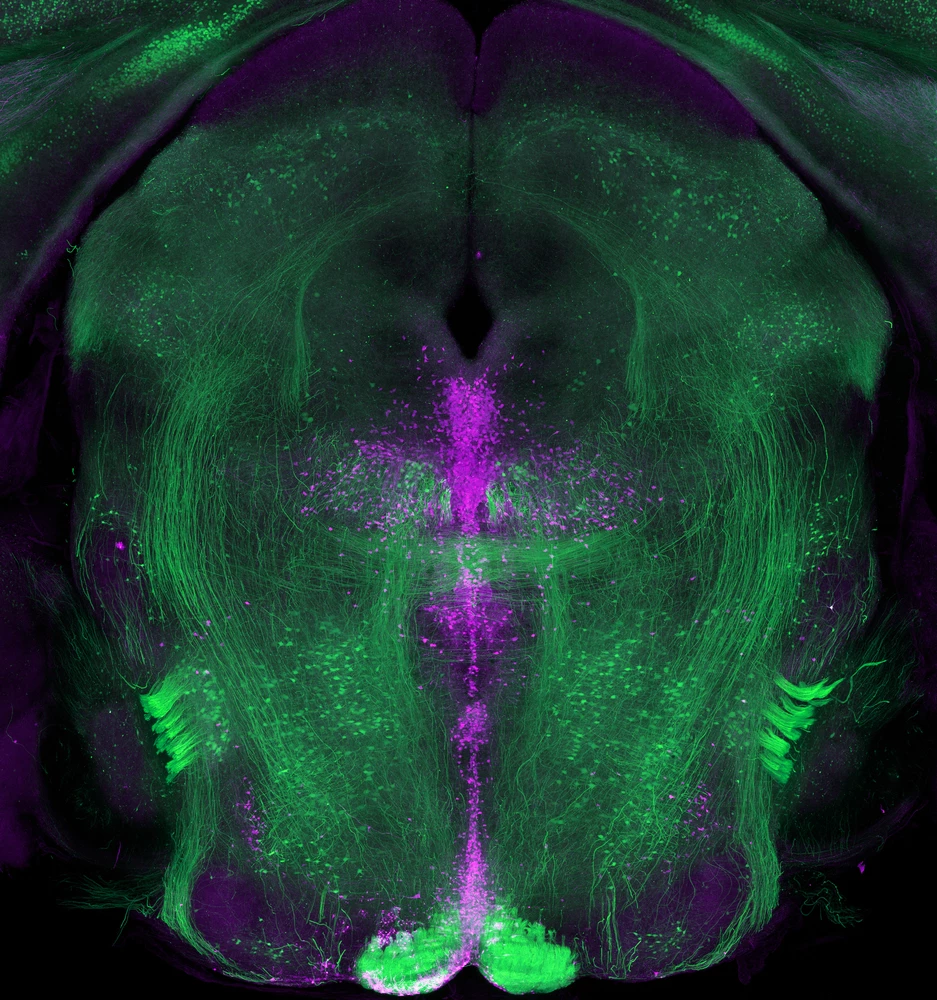

If the color purple makes you happy, you’re not alone. The purple cells in this image produce serotonin which plays a key role in the control of mood and emotions.

This image shows a 1.5-millimeter-thick coronal slice (from top to bottom) through the brain of a mouse, with neurons that produce serotonin (1 and 4) labeled in purple and pyramidal neurons (2) labeled in green. These clusters of serotonin-producing neurons (also known as serotonergic neurons) are located in an area of the brain called the raphe nucleus, just below the cerebral aqueduct (3), a fluid-filled canal in the midbrain.

Serotonin is a biochemical compound that contributes to a variety of important biological functions, including the regulation of mood and emotions as well as of body temperature. Most of the neurons that produce serotonin originate in an area of the brain called the raphe nucleus. The serotonergic neurons in the raphe nucleus send projections throughout the brain and spinal cord to supply serotonin wherever it’s needed.

Two areas that the neurons in the raphe nucleus send serotonin to are the hypothalamus and the cerebral cortex, both of which also play significant roles in regulating mood and emotion.

In mice and humans alike, the cell bodies of serotonergic neurons can vary in size from 15 micrometers across, or roughly five times smaller than the width of a human hair, to 60 micrometers across, or slightly smaller than the width of a human hair.

These images were created using confocal microscopy.